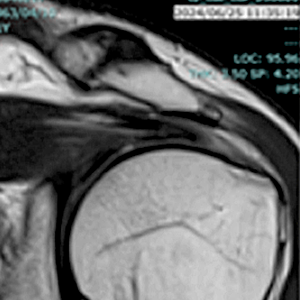

症例 2